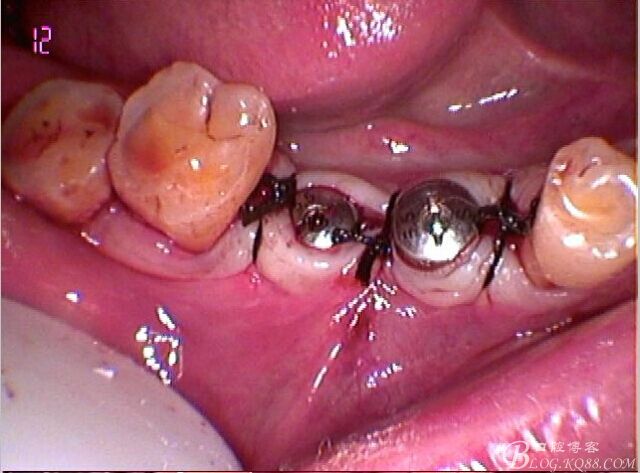

因為左上做過種植,口內見

C6頰側骨缺損凹陷,對合金屬全冠,

口外粘接后,口內螺絲固位

檢查邊緣封閉及靜態(tài)密合

牙齦封閉良好,咬合,近中觸點穩(wěn)定

樹脂封閉螺絲孔